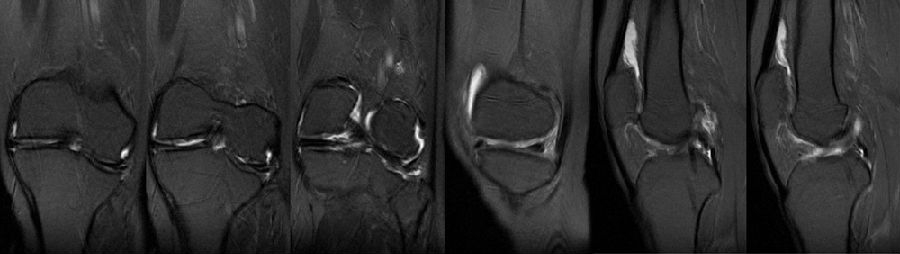

术前MR

该病例特点:患者中年女性,49岁,较活跃;JLCA基本正常,关节线倾斜,下肢力线略外翻;倾斜来源股骨内翻和胫骨外翻;既往股骨远端手术史;陈旧性软组织疤痕,局部畸形,骨质硬化,合页易骨折。